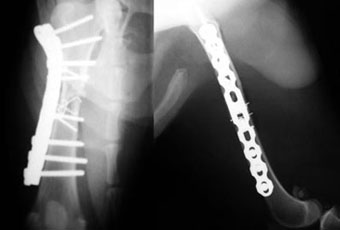

体重20kg、年齢13歳の犬の大腿骨粉砕骨折。

大腿骨中央部で砕けて、近位(股関節に近い側)と遠位(膝に近い側)と中央部5つの小骨片に分かれていました。

中央部の小骨片をラグスクリュー法と細ピン固定法でひとつに組み立ててから、近位−中央部−遠位の骨をバトレスプレート法で固定しました。このぐらいの年齢になると、プレートを外すことはありません。

写真上段: 手術前

写真下段: 手術後